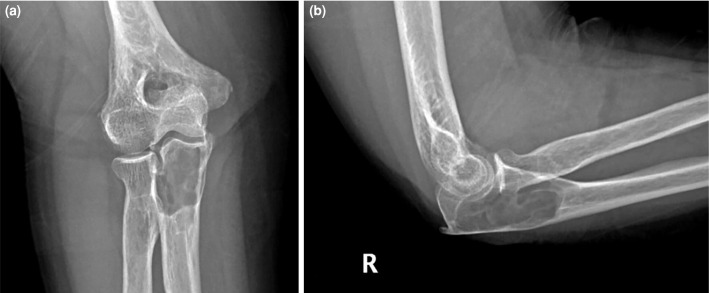

骨内神经鞘瘤是一种极为罕见的良性肿瘤,起源于周围神经系统的雪旺细胞。虽然这些肿瘤常见于下颌骨和骶骨,但它们发生在长骨,特别是尺骨,是罕见的。59岁女性患者因右肘疼痛和肿胀两年入院。x线影像学显示尺骨近端干骺端皮质扩张和变薄的溶解性病变,而磁共振成像显示不规则边界病变通过皮质侵蚀延伸到关节。鉴别诊断包括单纯性骨囊肿、内生纤维瘤、巨细胞瘤和转移。手术包括刮除和植骨,病理诊断为骨内神经鞘瘤。免疫组化染色显示SOX10和S100阳性表达,证实诊断。术后恢复顺利,患者在6个月的随访中恢复了全活动能力,无疼痛。总之,这个病例强调了在良性骨病变鉴别诊断中考虑骨内神经鞘瘤的重要性,特别是在罕见的部位,如尺骨。组织病理学检查仍然是准确诊断的必要条件。

Intraosseous schwannomas are extremely rare benign tumors originating from Schwann cells of the peripheral nervous system. While these tumors are commonly found in the mandible and sacrum, their occurrence in long bones, particularly the ulna, is uncommon. A 59-year-old female patient was admitted with a two-year history of pain and swelling in her right elbow. Radiographic imaging revealed a lytic lesion with cortical expansion and thinning in the proximal ulna metaphysis, while magnetic resonance imaging showed a lesion with irregular borders extending into the joint via cortical erosion. Differential diagnoses included a simple bone cyst, enchondroma, giant cell tumor, and metastasis. Surgical procedure involved curettage and bone grafting, and the lesion was diagnosed histologically as an intraosseous schwannoma. Immunohistochemical staining showed positive expression of SOX10 and S100, confirming the diagnosis. Postoperative recovery was uneventful, and the patient regained a full range of motion without pain at her six-month follow-up. In conclusion, this case underscores the importance of considering intraosseous schwannoma in the differential diagnosis of benign bone lesions, particularly in rare locations such as the ulna. Histopathological examination remains essential for an accurate diagnosis.